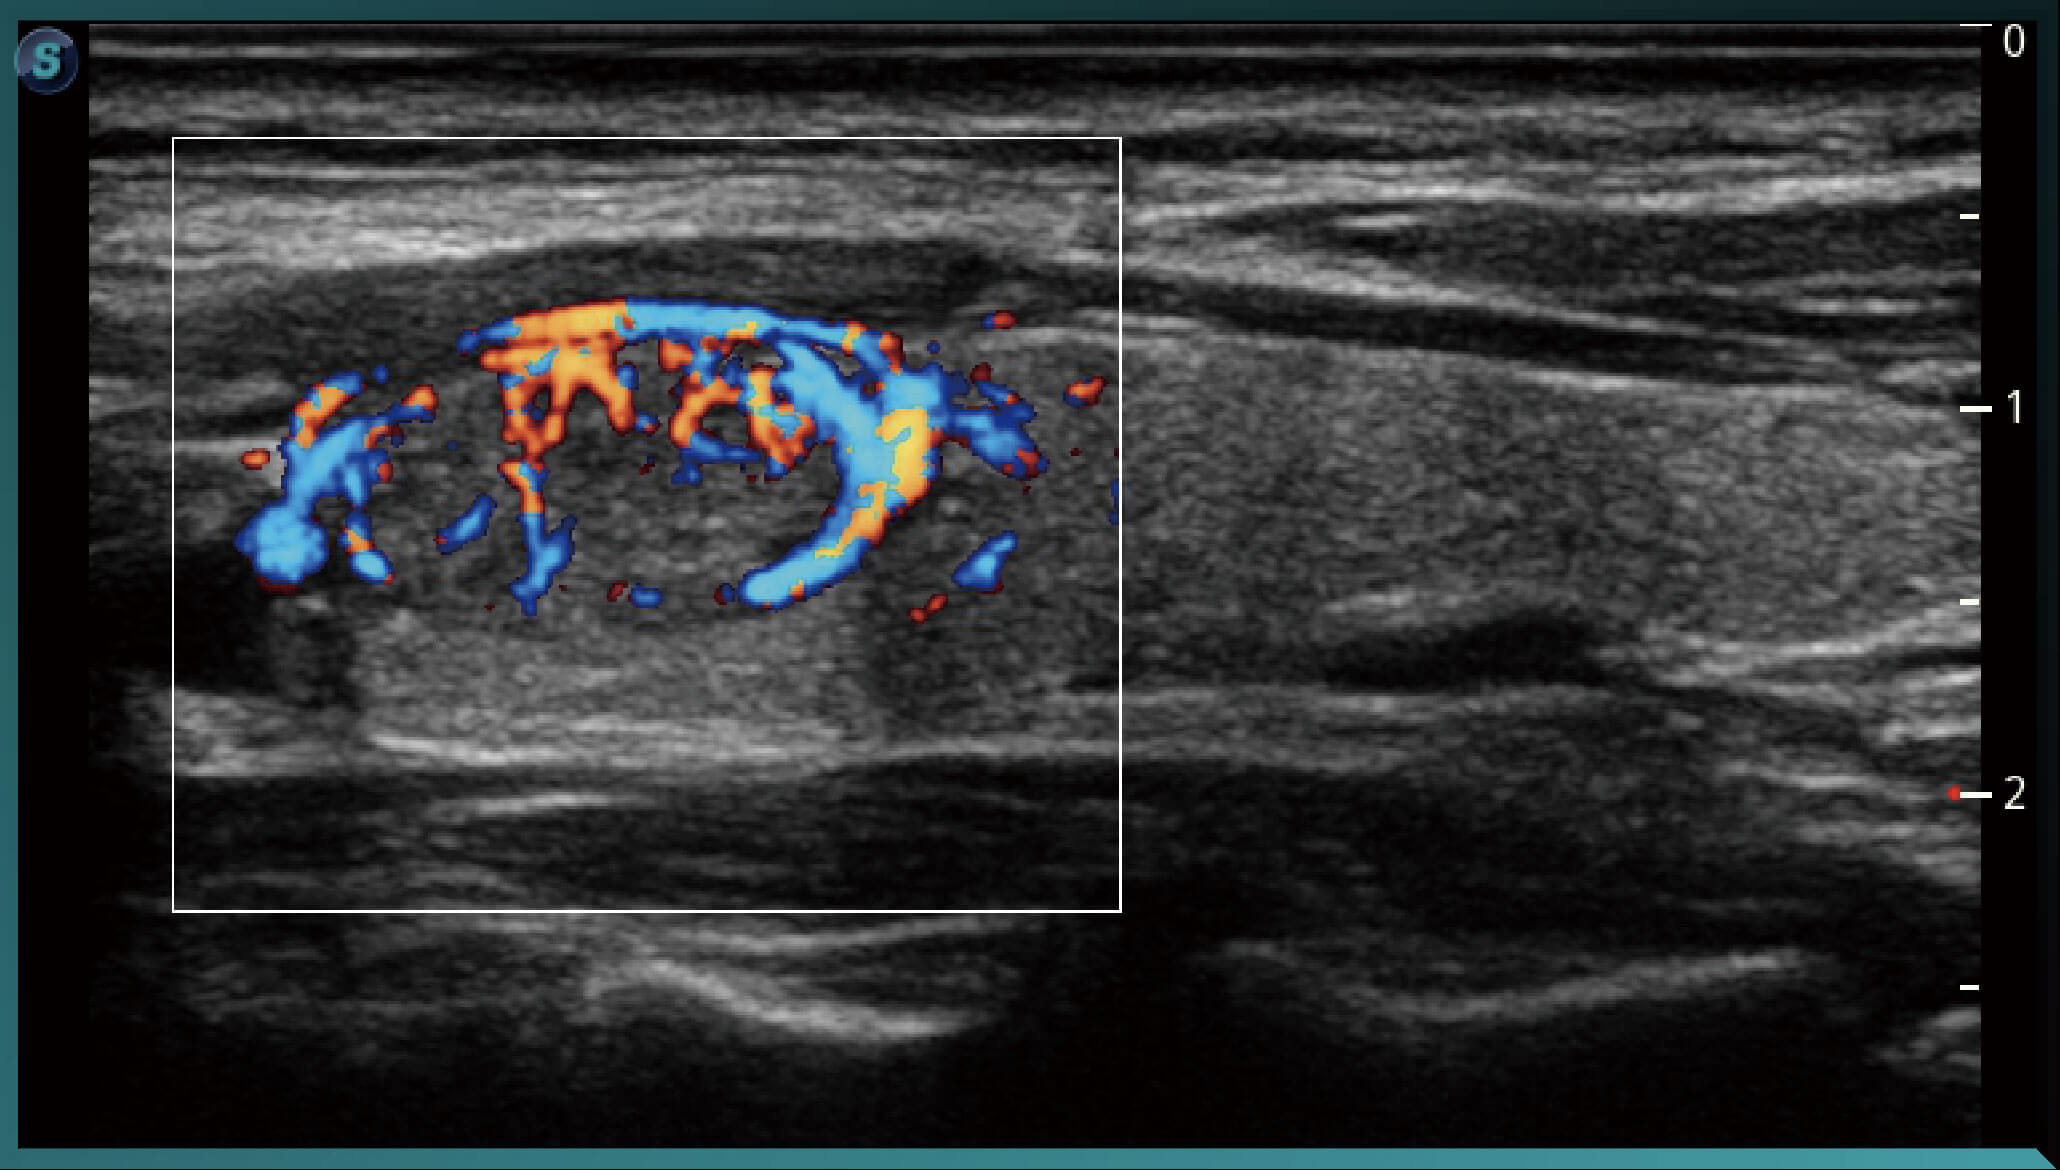

SR-Flow

Công nghệ lọc hiệu quả cao giúp hình ảnh hóa dòng chảy chậm, cho phép hiển thị Doppler sống động với độ nhạy cao.